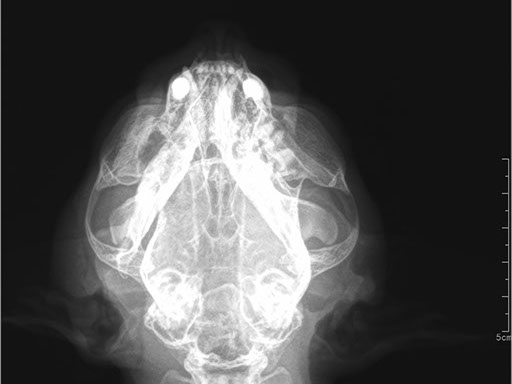

ЦИФРОВОЙ РЕНТГЕН В ВЕТЕРИНАРИИ